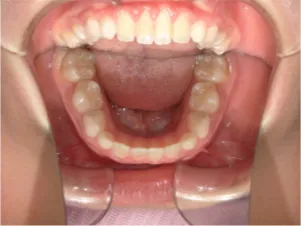

治療前①小5:スタート

| はじめのご相談 | 凸凹になりそうと一般歯科の先生に言われたのでみてほしい |

|---|---|

| カウンセリング・診断結果 | 下あごが後退しているタイプの出っ歯で、過蓋咬合で下あごが前に成長しにくいタイプの顔立ちです。 上の歯列弓が小さめで前歯に凸凹があります。 口元が閉じにくい口唇閉鎖不全があります。 *上記に対する治療の流れを説明し(拡大・前歯の並べ替え→出っ歯の改善→モノブロック装置(筋機能的咬合誘導装置)→必要によりマルチブラケット法)、以下の治療を提案しました。 |

| 行ったご提案・診断内容 | 成長期に行う治療と咬合治療をご提案しました。 成長期治療(成長時期にお口の環境を整え、適正な成長を促す治療)で、 ①歯列弓形態の修正、拡大と前歯を並べる。 ②出っ歯を治す専用の装置を使用する。 ③・MFT:舌や口唇などが正しい動きやポジショニングで機能し、鼻で呼吸できるようにする練習、毎日おうちで習慣づくように続けてもらいます。 ④拡大による顎顔面の適正な成長効果で口元を改善する(写真③)。 |